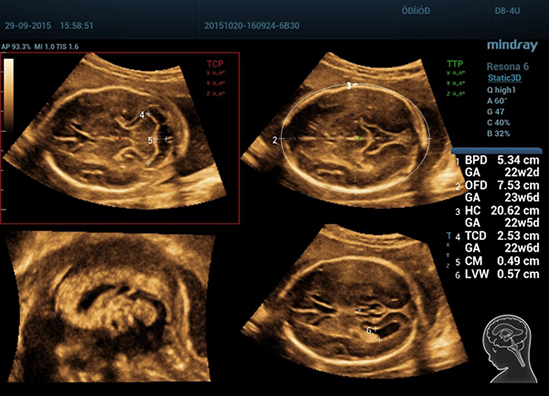

Клинические изображения Mindray Resona 6:

Обеспечивая качество изображения уровня премиум, Resona 6 также повышает клинические возможности исследования при помощи революционной системы V Flow, предназначенной для оценки гемодинамических показателей сосудов; обеспечивает интеллектуальное получение из 3D данных наиболее важных проекций для диагностики ЦНС плода. Сочетая в себе интуитивно понятное сенсорное управление с распознаванием жестов и все важные клинические характеристики, передовая система Resona 6 настоящая новая волна в сфере ультразвуковых инноваций.